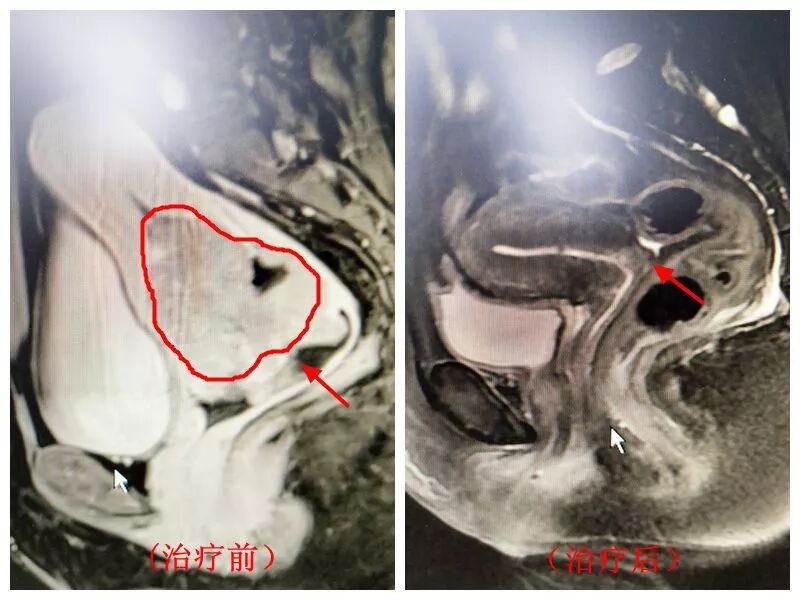

68岁王阿姨被某医院诊断为“宫颈癌ⅡB期”,这可吓坏了王阿姨的儿女,为了找到最佳治疗方案,儿女们可谓煞费苦心。经朋友介绍,他们带王阿姨来我院放射治疗科就诊。医生贾靖接诊了王阿姨,经进一步查体和辅助检查,发现王阿姨宫颈处有一“菜花型”病灶,大小为7.3cm×6.6cm ×5.6cm,随后病理结果证实王阿姨确实患上了宫颈鳞状细胞癌,并已发展到ⅡB期,贾医生建议王阿姨住院治疗。

经过一周的治疗,王阿姨的宫颈癌灶体积缩小至3.3cm×3.9cm× 3.6cm。立竿见影的治疗效果,更坚定了王阿姨的治疗信心。随后,王阿姨又接受了四周的放化疗联合治疗。检查发现,王阿姨体内的“菜花型”宫颈癌灶竟然奇迹般消失了。